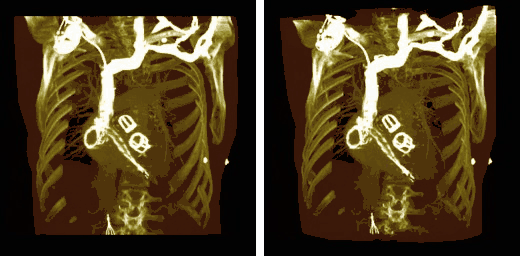

Volume rendering can be applied to the voxel data in the successive rotation manner described for MIPs above, as illustrated by the results in the following figure:

Note that the volume rendering can be contrast enhanced so as to threshold, for instance, through the voxel values to eliminate low attenuating surfaces, as illustrated in the following figure: